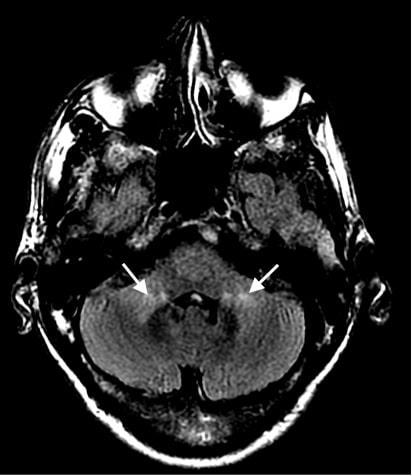

ATYPICAL PRESENTATION AND DIAGNOSIS OF AIDS-RELATED CMV ENCEPHALITIS

Erick Kawegere1, Tamara Goldberg1

1Mount Sinai Morningside-West Hospitals, Icahn School of Medicine at Mount Sinai, New York, NY, United States

Published in BMJ Case Reports, 2022. PMID: 36041775 35